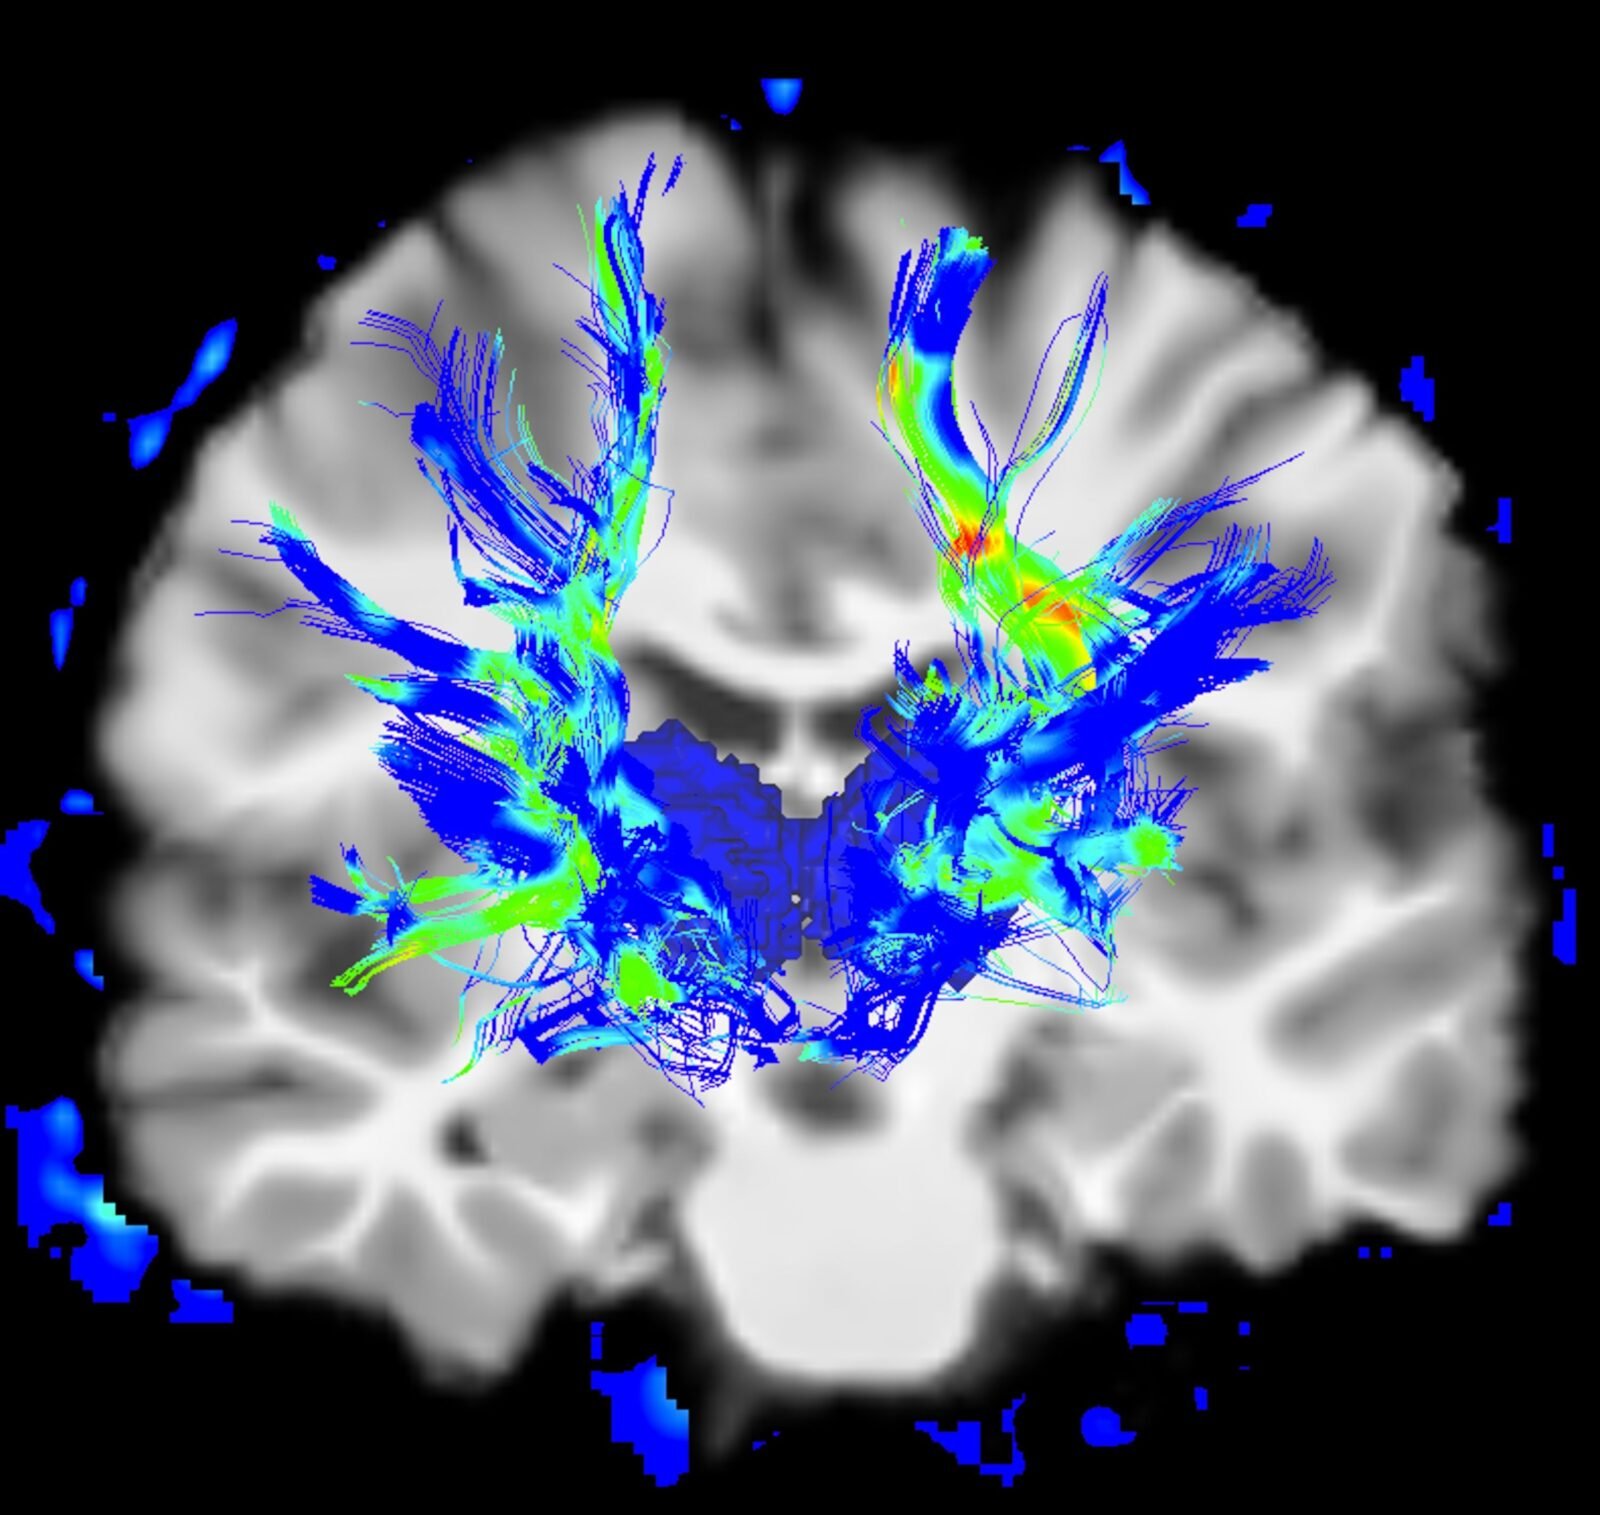

Científicos identifican una red cerebral que podría revolucionar el tratamiento del Parkinson

«Modificar la actividad de la red cerebral SCAN podría ralentizar o revertir la progresión de la enfermedad de Parkinson, no solo tratar los síntomas”, afirman los autores de este nuevo estudio.